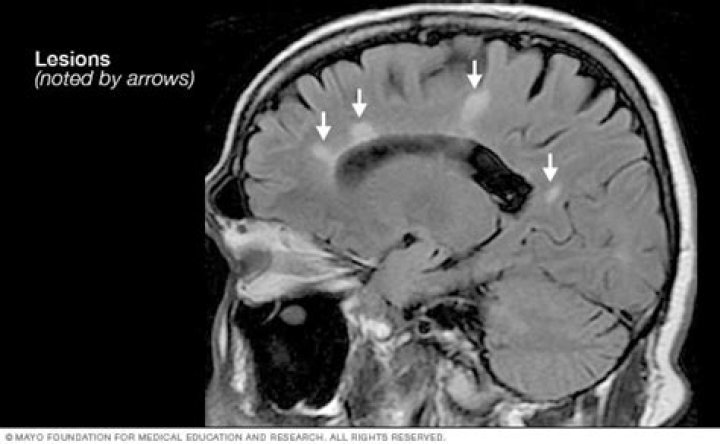

What is the McDonald criteria for MS diagnosis?

Under the McDonald Criteria (revised), an MS diagnosis is likely if myelin damage is disseminated in space, as seen in an MRI as: At least one T2 bright lesion in at least two or four CNS locations: the juxtacortical, perventricular and infratentorial areas of the brain, and the spinal cord.

Do MS lesions come and go?

“Paradoxically, we see that lesion volume goes up in the initial phases of the disease and then plateaus in the later stages,” Zivadinov says. “When the lesions decrease over time, it’s not because the patient lesions are healing but because many of these lesions are disappearing, turning into cerebrospinal fluid.”